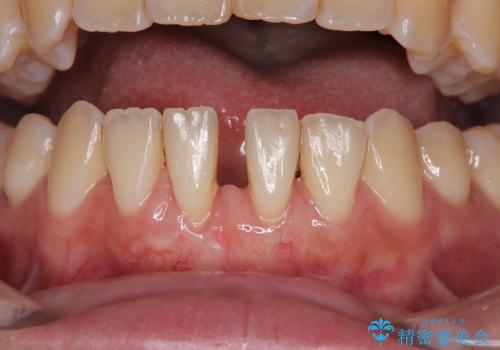

矯正の後戻りによるすきっ歯と歯肉退縮 根面被覆と部分矯正

- 学生時代の矯正治療の後戻りと、それに伴う下顎前歯西肉退縮を気にして来院された患者様です。

舌の突出癖が著しく、それが原因で後戻りと歯肉退縮を起こしている状態でした。

舌のトレーニングをしっかりと行っていくことを前提に、歯肉移植による根面被覆と、部分矯正によるすきっ歯の改善を行うこととしました。